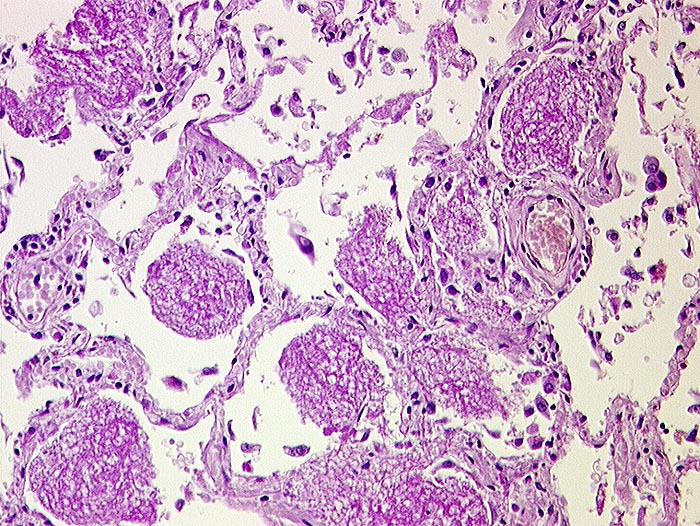

Bei Pneumocystis carinii handelt es sich um eine Pilzinfektion. Die Organismen sind in intraalveolärem schaumigem Material nachweisbar. Dieses flockig-schaumige Material färbt sich in der Papanicolaou Färbung eosinophil oder basophil. Die Erreger selbst sind in der Papanicolaou Färbung nur schlecht sichtbar. Die Zysten lassen sich aber mit der Grocott-Versilberung darstellen. Sie sind 4 bis 8 Mikrometer gross, rundoval und enthalten einen zentralen schwarzen Punkt. Die Zysten enthalten bis zu acht 0.5 bis 1 Mikrometer messende Trophozoiten.